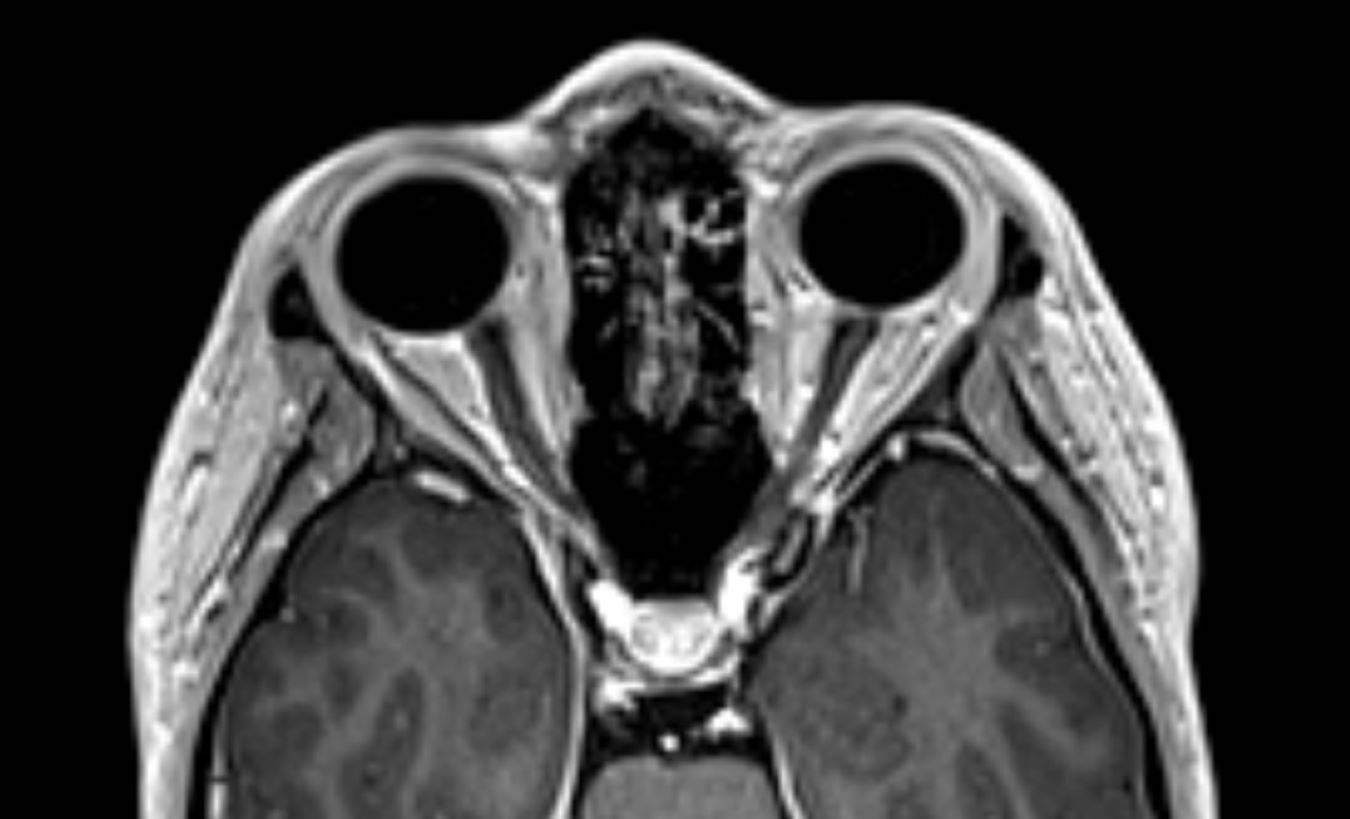

Die (MRT) scanCT Scans von menschlichen Kopf auf einem Ultraschall from www.alamy.de

Die (MRT) scanCT Scans von menschlichen Kopf auf einem Ultraschall ich war beim MRT heute weil ich Wahrnehmungsstörungen bekommen habe und Kopfschmerzen CT vor 2 Wochen Negativ und jetzt MRT auch negativ aber wurde ohne Kontrastmittel gemacht Die Hauptindikationen für die Diagnose: Schlaganfall (hämorrhagisch, ischämisch).